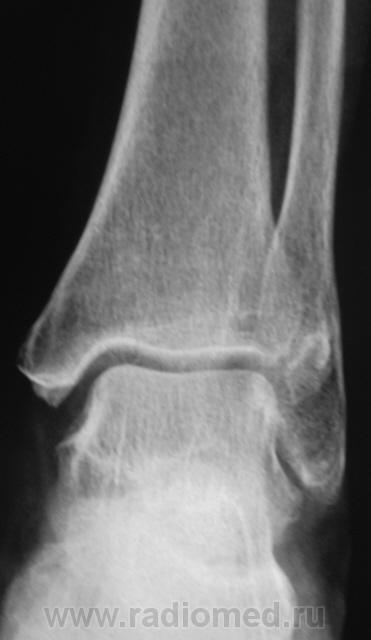

на консолидированный перелом Фолькмановского клина б\берцовой кости.

А, может быть, с учетом деформации малоберцовой кости, на боковой рентгенограмме, можно предположить, что, "это", откол фрагмента костной ткани от дистального эпифиза б/берцовой кости.

Если говорить о травме ( нужно учесть механизм), то можно предположить вдавленный перелом с огранич., но интенс. действием травмирующей силы с компрессией ( уплотнением) костной ткани.